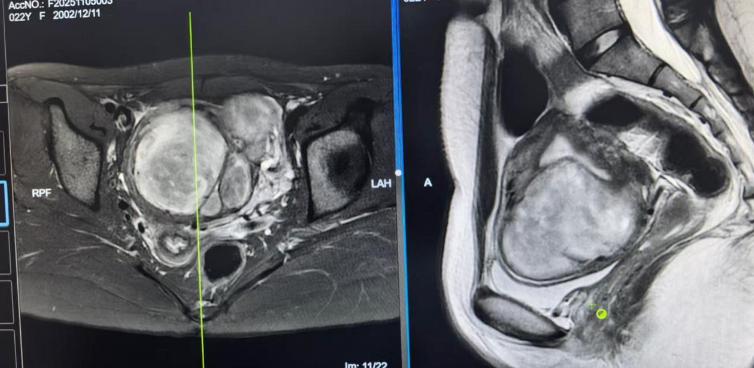

患者核磁影像